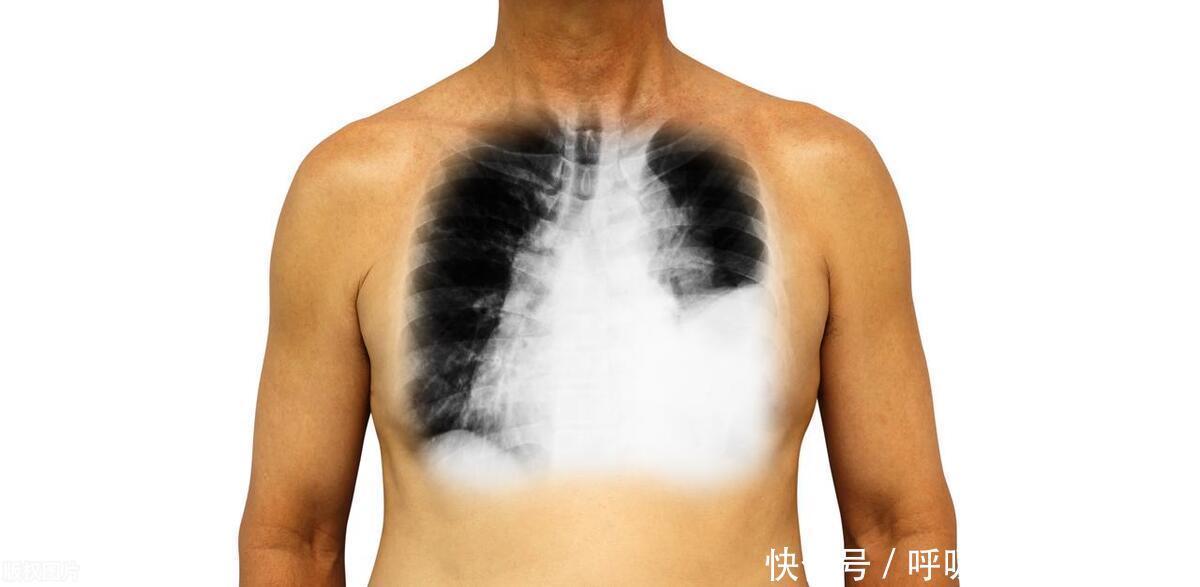

在癌症的王国里,肺癌就像一个冷酷无情的“杀手”,悄然威胁着人们的生命健康。而在中国,肺癌的发病率和死亡率更是居高不下,这让人们不禁要问:为什么中国的肺癌患者越来越多?

我们可以把肺癌比作一个狡猾的“敌人”,它善于隐藏自己,让人们难以察觉。而抽烟、空气污染、职业暴露、电离辐射等因素,就像是“敌人”的帮凶,助其在人体内肆意妄为。